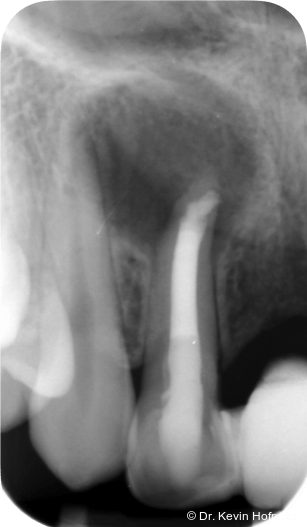

Klinisch zeigten sich die Zähne 12 und 13 karies- und füllungsfrei. Zahn 12 reagierte nicht auf Sensibilitätstests und war leicht perkussionsempfindlich. Zahn 13 reagierte unauffällig. Radiologisch zeigte sich eine ausgedehnte apikale Aufhellung am Zahn 12 sowie eine Hartgewebsformation im apikalen Kanallumen (Abb. 1–2d).

Geplant wurde eine Wurzelkanalbehandlung an Zahn 12. Die zunächst vorgesehene Zystektomie mit Wurzelspitzenresektion wurde zurückgestellt, um die Heilungstendenz nach orthograder Therapie zu beurteilen und einen chirurgischen Eingriff möglichst zu vermeiden.